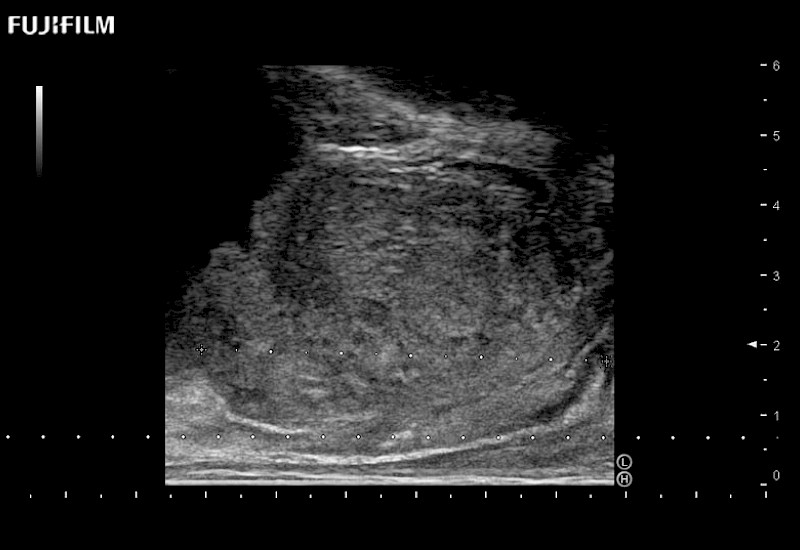

38mm footprint is ideal for scrotal and penile doppler imaging

Main Specifications:

Larger footprint is ideal for scrotal and penile doppler imaging